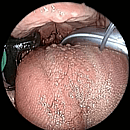

COBLATION Assisted Surgeries

A minimally invasive, low thermal technology for effective dissection and removal of tissue, COBLATION Technology has been used for ENT procedures such as tonsillectomy, turbinate reduction, laryngeal lesion debulking and soft palate.

While conventional electrosurgical devices use high temperatures to remove and cut tissue, our COBLATION Technology creates a controlled, stable plasma field to precisely remove tissue at a low relative temperature, resulting in minimal thermal damage to surrounding soft tissues. Its features include very limited depth of thermal penetration; minimal collateral tissue damage; localised effect; and controlled, volumetric tissue removal. Coblation is often preferred for its ability to reduce surgery duration and pain, minimise bleeding, and speed up recovery times in patients undergoing certain types of surgery.